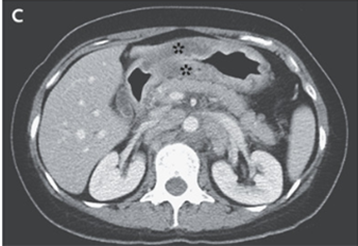

悪性腫瘍検索のため内科紹介となり、CT施行。異体の壁肥厚(下記星印)を認めた。